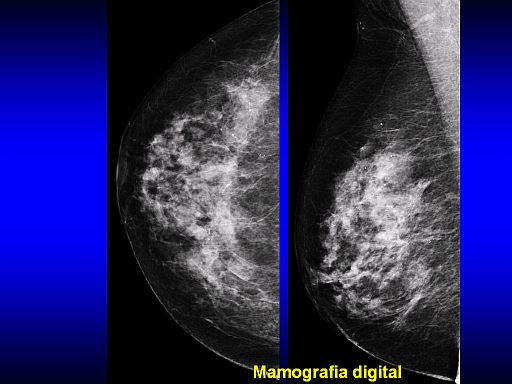

Na opinião de Aron Belfer, em termos de tecnologia, a mamografia digital 2D é um avanço importante em relação à mamografia analógica, convencional. Já a tomossíntese, de acordo com estudos recentes, surge como uma tecnologia capaz de detectar lesões que antes passariam despercebidas na mamografia digital 2D. “A detecção de tumores menores permite recorrer a cirurgias menos mutilantes, resulta em menor custo global do tratamento, maior sobrevida e melhor qualidade de vida das pacientes”.